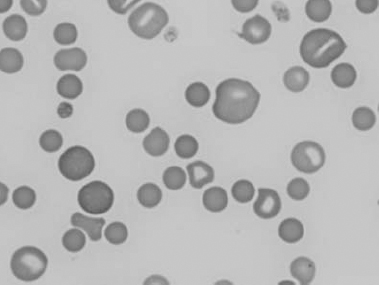

See Figs 1.3–1.24 for pictures of various types of RBC morphology.

Figure 1.3 Canine blood film showing acanthocytes (also see color section).

Figure 1.4 Canine blood film showing anisocytosis (also see color section).

Figure 1.5 Bovine blood film showing basophilic stippling within a macrocyte as part of the regenerative response (also see color section).

Figure 1.6 Canine blood film showing basophilic stippling due to lead toxicosis (also see color section).

Figure 1.7 Canine blood film showing blister cells due to oxidative damage (also see color section).

Figure 1.8 Canine blood film showing codocytes. Up to 50% codocytes may be normal in a dog (also see color section).

Figure 1.9 Canine blood film showing eccentrocytes due to oxidative damage (also see color section).

Figure 1.10 Canine blood film showing echinocytes I (also see color section).

Figure 1.11 Canine blood film showing echinocytes III (also see color section).

Figure 1.12 Feline blood film showing echinoelliptocytes (also see color section).

Figure 1.13 Canine blood film showing Heinz bodies and ghost cells due to oxidative damage. There are also several polychromatophils (also see color section).

Figure 1.14 Canine blood film stained with new methylene blue, to demonstrate Heinz bodies (also see color section).

Figure 1.15 Canine blood film showing keratocytes and schizocytes (erythrocyte fragments) due to fibrin strand injury. A codocyte and a polychromatophil also appear in the field (also see color section).

Figure 1.16 Feline blood film showing Mycoplasma hemofelis organisms (hemobartonellosis). Organisms are not always visible in blood smears from infected cats (also see color section).

Figure 1.17 Canine blood film showing several macrocytes (also see color section).

Figure 1.18 Canine blood film showing a metarubricyte There is also a polychromatophilic macrocyte in the field (also see color section).

Figure 1.19 Canine blood film showing microcytic, hypochromic erythrocytes consistent with iron deficiency anemia. There are two polychromatophils in the field, indicating that the anemia is regenerative (also see color section).

Figure 1.20 Canine blood film showing two macrocytes with nuclear remnants (also see color section).

Figure 1.21 Bovine (calf) blood film showing marked poikilocytosis (normal?) (also see color section).

Figure 1.22 New methylene-blue-stained Canine blood film showing reticulocytes (also see color section).

Figure 1.23 Canine blood film showing rouleaux formation (also see color section).

Figure 1.24 Canine blood film showing spherocytosis and polychromasia due to immune-mediated hemolytic anemia (also see color section).

Figure 1.25 The red blood cell cytoskeleton.